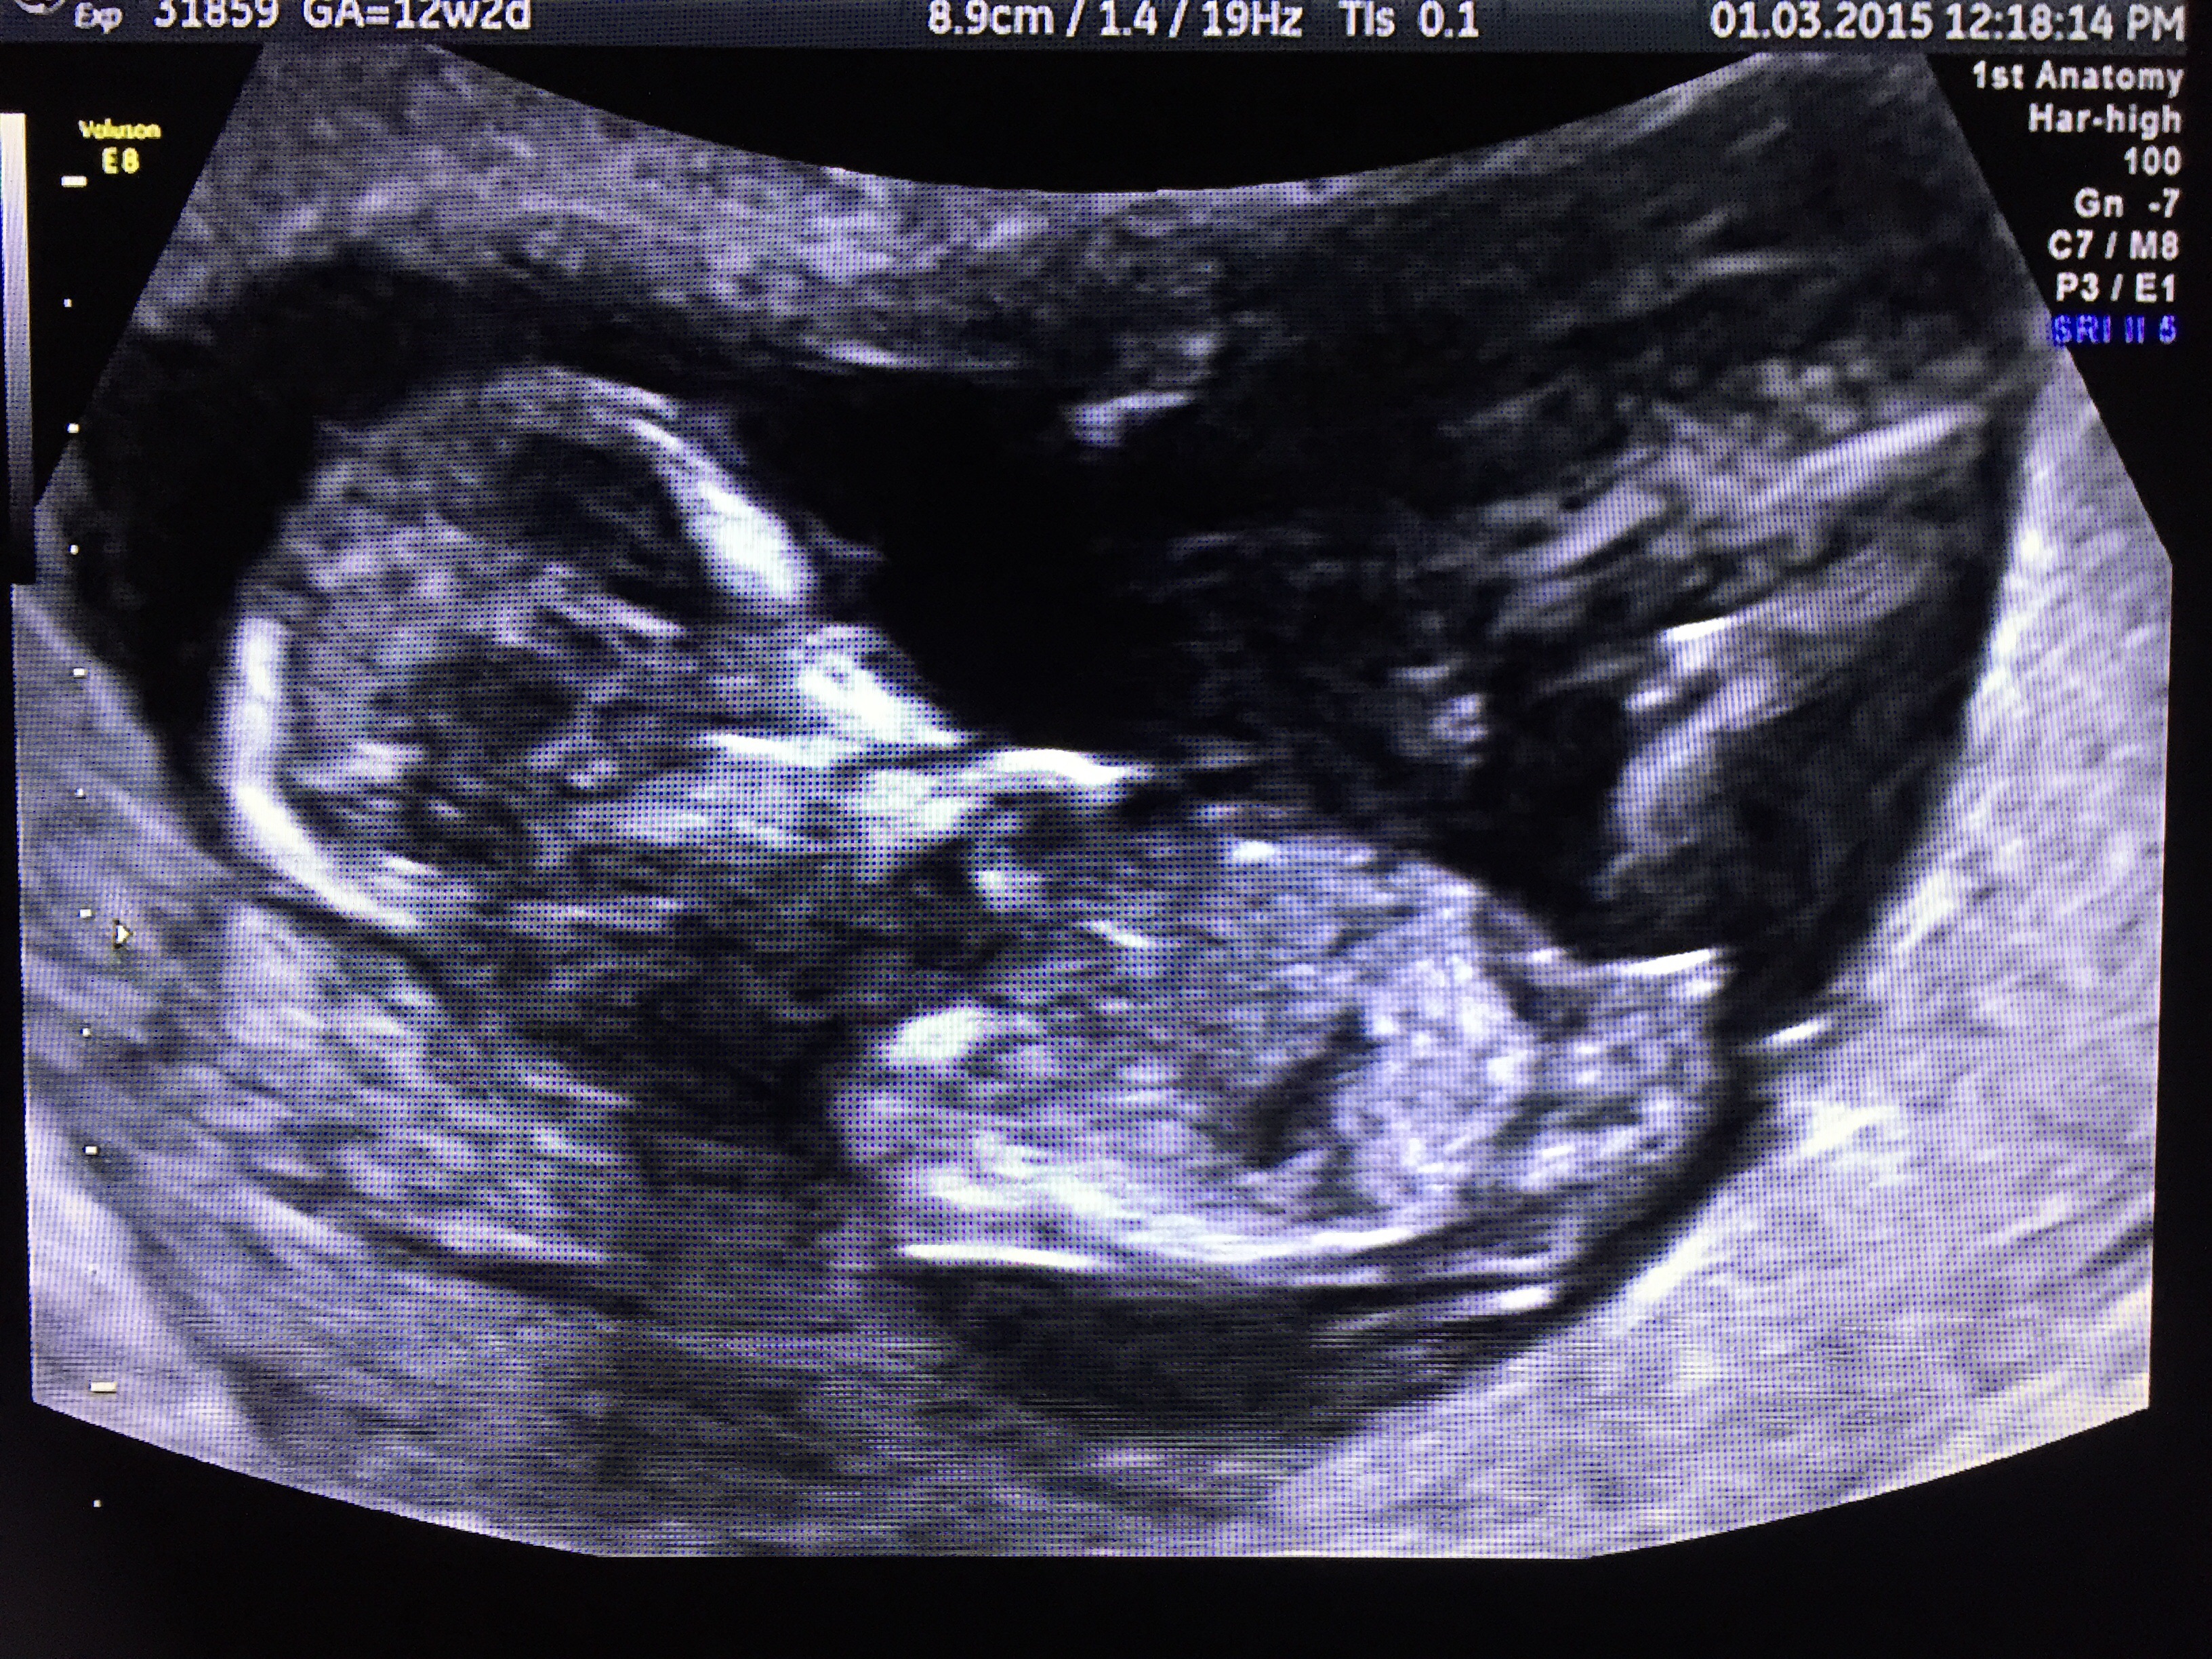

I took the screenshots myself from the video the doctor gave me, I'm not an expert so I tried to pause at exactly the frame which I thought looked like a nub but I could be wrong. I also took another screenshot from the video of the baby's bottom with legs protruding. What do you guys think?Attachment 23974